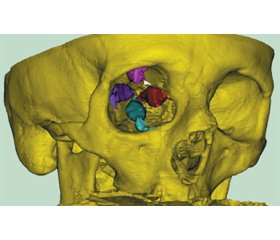

Актуальність. Ендокринна орбітопатія (ЕО) зустрічається в молодих осіб працездатного віку, негативно впливає на якість життя, може призвести до втрати зору, що є медико-соціальною проблемою. При тяжкому й середньому ступені тяжкості ендокринної орбітопатії застосовують хірургічну декомпресію, частота ускладнень якої становить від 9,3 до 35 %. На сьогодні пошук нових можливостей для профілактики післяопераційних ускладнень є актуальною проблемою щелепно-лицевої хірургії та офтальмології. Мета: оцінити результати лікування та визначити частоту ускладнень при проведенні декомпресії орбіти з використанням хірургічних навігаційних шаблонів при лікуванні пацієнтів з ендокринною орбітопатією. Матеріали та методи. Проведено аналіз результатів декомпресії орбіти у 17 пацієнтів з ЕО, що проходили лікування на базі Київської обласної клінічної лікарні та Київської міської клінічної лікарні № 1 в період з 2017 по 2021 р. Для проведення дослідження нами був використаний відповідний цифровий протокол. Результати. За даними передопераційної екзофтальмометрії, середня величина екзофтальму на правому та лівому оці становила 23,75 ± 3,07 мм і 24,27 ± 3,26 мм відповідно. В післяопераційному періоді виявлено, що середня величина екзофтальму для правого ока становила 18,88 ± 2,18 мм, для лівого — 19,47 ± 3,01 мм; статистично вірогідної відмінності в обстежуваній групі також не було виявлено (p = 0,892). Середня величина зменшення екзофтальму в досліджуваній групі — 4,84 ± 0,27 мм. За допомогою методів варіативної статистики нами було підтверджено вірогідне зменшення величини екзофтальму в досліджуваній групі порівняно з передопераційними показниками (р < 0,001). Серед післяопераційних ускладнень у терміни спостереження 3 місяці в одного хворого нами спостерігалася диплопія, а після лікування трьох пацієнтів зберігалася гіпестезія у зоні іннервації ІІ гілки трійчастого нерва. При проведенні декомпресії 5 орбіт було виявлено незначну кровотечу, що не потребувала додаткових методів зупинки. При цьому в жодному випадку ми не спостерігали такого загрозливого післяопераційного ускладнення, як лікворея. Висновки. При лікуванні пацієнтів з ЕО використання CAD/CAM технології дозволяє вдосконалити етап планування оперативного втручання завдяки можливості віртуальної симуляції кісткової декомпресії орбіти на передопераційному етапі. Використання хірургічних навігаційних шаблонів при декомпресії орбіти в лікуванні ендокринної орбітопатії дозволяє досягти суттєвого зменшення екзофтальму (у середньому на 4,84 ± 0,27 мм) на фоні зменшення площі кісткової резекції, що знижує ризик післяопераційних ускладнень.

Background. Endocrine orbitopathy occurs in young people of working age, negatively affects the quality of life, can lead to vision loss, which is a medical and social problem. Surgical decompression is used for severe and moderate endocrine orbitopathy, its complication rate ranges from 9.3 to 35 %. Today, the search for new options to prevent postoperative complications is an urgent problem of maxillofacial surgery and ophthalmology. Objective: to evaluate the results of treatment and determine the frequency of complications during orbital decompression using surgical guides for the management of patients with endocrine orbitopathy. Materials and methods. To achieve this goal, an analysis of the results of orbital decompression was performed in 17 patients with endocrine orbitopathy treated at the Kyiv Regional Clinical Hospital and Kyiv City Clinical Hospital 1 from 2017 to 2021. We used the appropriate digital protocol to conduct the study. Results. According to preoperative exophthalmometry, the average value of exophthalmos in the right and left eyes was 23.75 ± 3.07 mm and 24.27 ± 3.26 mm, respectively. In the postoperative period, the average value of exophthalmos for the right eye was 18.88 ± 2.18 mm, for the left 19.47 ± 3.01 mm; there we no statistically significant differences in the study group (p = 0.892). The average reduction of exophthalmos in the study group was 4.84 ± 0.27 mm with significant difference between pre- and postoperative values (p < 0.001). Among the postoperative complications during the observation period of 3 months, diplopia was detected in one patient, and hypoesthesia in the area of innervation of the second branch of the trigeminal nerve after treatment remained in three patients. During the decompression of 5 orbits, there was a minor bleeding, which did not require additional methods to stop it. We didn’t observe such threatening postoperative complication as cerebrospinal fluid leak at all. Conclusions. In the treatment of patients with endocrine orbitopathy, the use of CAD/CAM technology allows improving the planning of surgical intervention due to the possibility of virtual simulation of bone decompression of the orbit at the preoperative stage. The use of surgical guides during orbital decompression allows achieving a significant reduction in exophthalmos (on average by 4.84 ± 0.27 mm) against the background of reducing the area of bone resection, which can potentially decrease the risk of postoperative complications.